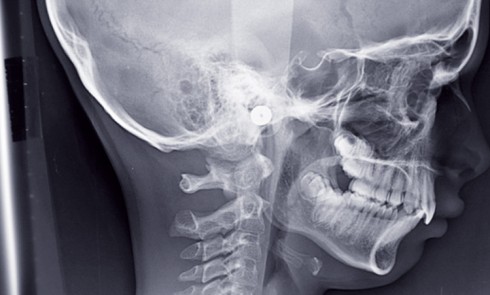

Ronflements et apnées du sommeil sont largement sous-estimés en France alors qu’il est établi qu’ils peuvent être à l’origine de...

Les Dysfonctionnements de l’Appareil Manducateur (DAM), aussi appelés Algies et Dysfonctionne-ments de l’Appareil Manducateur (ADAM) ou Dysfonctionnements Temporo-Mandibulaires (DTM), regroupent...